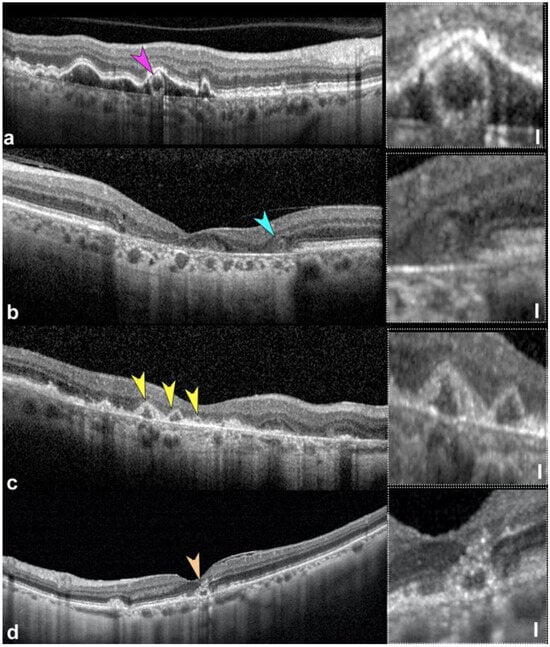

2.3. Outer Retinal Tubulations

- Fragiotta, S.; Parravano, M.; Sacconi, R.; Costanzo, E.; De Geronimo, D.; Prascina, F.; Capuano, V.; Souied, E.H.; Han, I.C.; Mullins, R.; et al. Sub-retinal pigment epithelium tubules in non-neovascular age-related macular degeneration. Sci. Rep. 2022, 12, 15198. [Google Scholar] [CrossRef]

- Ooto, S.; Vongkulsiri, S.; Sato, T.; Suzuki, M.; Curcio, C.A.; Spaide, R.F. Outer retinal corrugations in age-related macular degeneration. JAMA Ophthalmol. 2014, 132, 806–813. [Google Scholar] [CrossRef]

- Fleckenstein, M.; Charbel Issa, P.; Helb, H.M.; Schmitz-Valckenberg, S.; Finger, R.P.; Scholl, H.P.; Loeffler, K.U.; Holz, F.G. High-resolution spectral domain-OCT imaging in geographic atrophy associated with age-related macular degeneration. Investig. Ophthalmol. Vis. Sci. 2008, 49, 4137–4144. [Google Scholar] [CrossRef]

- Zweifel, S.A.; Engelbert, M.; Laud, K.; Margolis, R.; Spaide, R.F.; Freund, K.B. Outer retinal tubulation: A novel optical coherence tomography finding. Arch. Ophthalmol. 2009, 127, 1596–1602. [Google Scholar] [CrossRef]

- Litts, K.M.; Messinger, J.D.; Dellatorre, K.; Yannuzzi, L.A.; Freund, K.B.; Curcio, C.A. Clinicopathological correlation of outer retinal tubulation in age-related macular degeneration. JAMA Ophthalmol. 2015, 133, 609–612. [Google Scholar] [CrossRef]

- Litts, K.M.; Wang, X.; Clark, M.E.; Owsley, C.; Freund, K.B.; Curcio, C.A.; Zhang, Y. Exploring Photoreceptor Reflectivity through Multimodal Imaging of Outer Retinal Tubulation in Advanced Age-Related Macular Degeneration. Retina 2017, 37, 978–988. [Google Scholar] [CrossRef] [PubMed]

- Schaal, K.B.; Freund, K.B.; Litts, K.M.; Zhang, Y.; Messinger, J.D.; Curcio, C.A. Outer Retinal Tubulation in Advanced Age-Related Macular Degeneration: Optical Coherence Tomographic Findings Correspond to Histology. Retina 2015, 35, 1339–1350. [Google Scholar] [CrossRef]

- Dolz-Marco, R.; Litts, K.M.; Tan, A.C.S.; Freund, K.B.; Curcio, C.A. The evolution of outer retinal tubulation, a neurodegeneration and gliosis prominent in macular diseases. Ophthalmology 2017, 124, 1353–1367. [Google Scholar] [CrossRef]

- Jung, J.J.; Freund, K.B. Long-term follow-up of outer retinal tubulation documented by eye-tracked and en face spectral-domain optical coherence tomography. Arch. Ophthalmol. 2012, 130, 1618–1619. [Google Scholar] [CrossRef]

- Wolff, B.; Matet, A.; Vasseur, V.; Sahel, J.A.; Mauget-Faysse, M. En Face OCT Imaging for the Diagnosis of Outer Retinal Tubulations in Age-Related Macular Degeneration. J. Ophthalmol. 2012, 2012, 542417. [Google Scholar] [CrossRef]

- Litts, K.M.; Ach, T.; Hammack, K.M.; Sloan, K.R.; Zhang, Y.; Freund, K.B.; Curcio, C.A. Quantitative Analysis of Outer Retinal Tubulation in Age-Related Macular Degeneration From Spectral-Domain Optical Coherence Tomography and Histology. Investig. Ophthalmol. Vis. Sci. 2016, 57, 2647–2656. [Google Scholar] [CrossRef]

- Litts, K.M.; Messinger, J.D.; Freund, K.B.; Zhang, Y.; Curcio, C.A. Inner Segment Remodeling and Mitochondrial Translocation in Cone Photoreceptors in Age-Related Macular Degeneration With Outer Retinal Tubulation. Investig. Ophthalmol. Vis. Sci. 2015, 56, 2243–2253. [Google Scholar] [CrossRef]